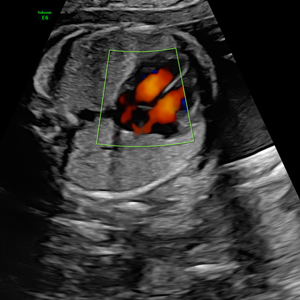

- Pionero en México en ofrecer diagnóstico por ultrasonido dentro del consultorio, así como en incorporar tecnología 3D y Doppler.